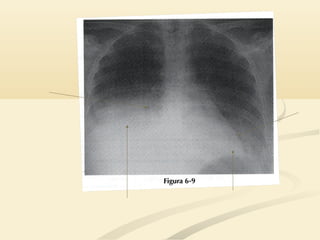

 Existe un signo de la silueta “normal” en la radiografía lateral.Existe un signo de la silueta “normal” en la radiografía lateral.

 El corazón está situado predominantemente sobre elEl corazón está situado predominantemente sobre el

hemidiafragma izquierdo anterior. Ambas estructuras tienenhemidiafragma izquierdo anterior. Ambas estructuras tienen

densidad agua; por lo tanto la parte anterior del hemidiafragmadensidad agua; por lo tanto la parte anterior del hemidiafragma

izquierdo no suele ser visible.izquierdo no suele ser visible.

 En la radiografía lateral, el hemidiafragma derecho esEn la radiografía lateral, el hemidiafragma derecho es

visible a través del corazón porque está en contacto convisible a través del corazón porque está en contacto con

pulmón aireado.pulmón aireado.

 Esto ayuda a distinguir el hemidifragma izquierdo delEsto ayuda a distinguir el hemidifragma izquierdo del

derecho en la radiografía lateralderecho en la radiografía lateral

 Existe unsigno de la silueta “normal” en la radiografía lateral.Existe un signo de la silueta “normal” en la radiografía lateral.  El corazón está situado predominantemente sobre elEl corazón está situado predominantemente sobre el hemidiafragma izquierdo anterior. Ambas estructuras tienenhemidiafragma izquierdo anterior. Ambas estructuras tienen densidad agua; por lo tanto la parte anterior del hemidiafragmadensidad agua; por lo tanto la parte anterior del hemidiafragma izquierdo no suele ser visible.izquierdo no suele ser visible.

• 27.

 En laradiografía lateral, el hemidiafragma derecho esEn la radiografía lateral, el hemidiafragma derecho es visible a través del corazón porque está en contacto convisible a través del corazón porque está en contacto con pulmón aireado.pulmón aireado.  Esto ayuda a distinguir el hemidifragma izquierdo delEsto ayuda a distinguir el hemidifragma izquierdo del derecho en la radiografía lateralderecho en la radiografía lateral